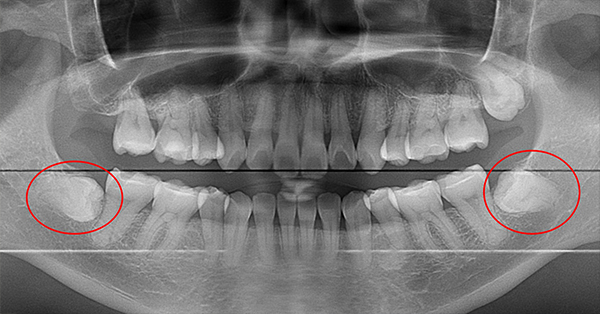

パノラマレントゲンデータ

精密なCTデータで状態把握

親知らずが横向きに生えていて、隣の歯を圧迫している埋伏歯の抜歯ケースです。このタイプは、抜歯が難しい分類になります。